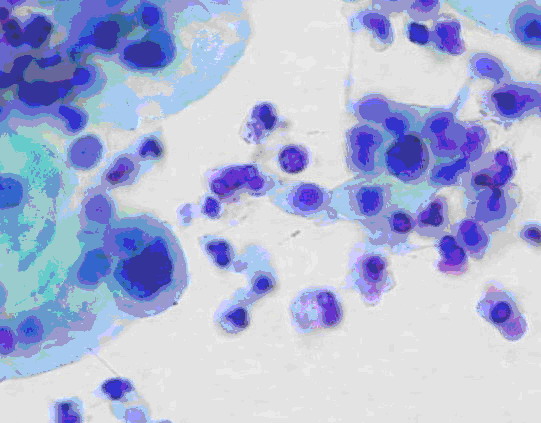

举例来说,慢性宫颈炎(宫颈糜烂)与宫颈癌在妇科阴道镜检查时观察到的表现可以相似。行宫颈刮片的细胞检查时看到的也可以相似(图1、2)。最后采取组织行病理切片检查,也是有相似之处,不是容易做出100%鉴别的(图3、4)。这样看来,如果仅一次检查(或一家医院检查),就肯定是癌,而行手术切除,是不慎重的,错误率是高的。最好是如果要手术切除,应到第二家医院或第二个医生核实后进行下一步治疗。

图1 宫颈炎看到的细胞